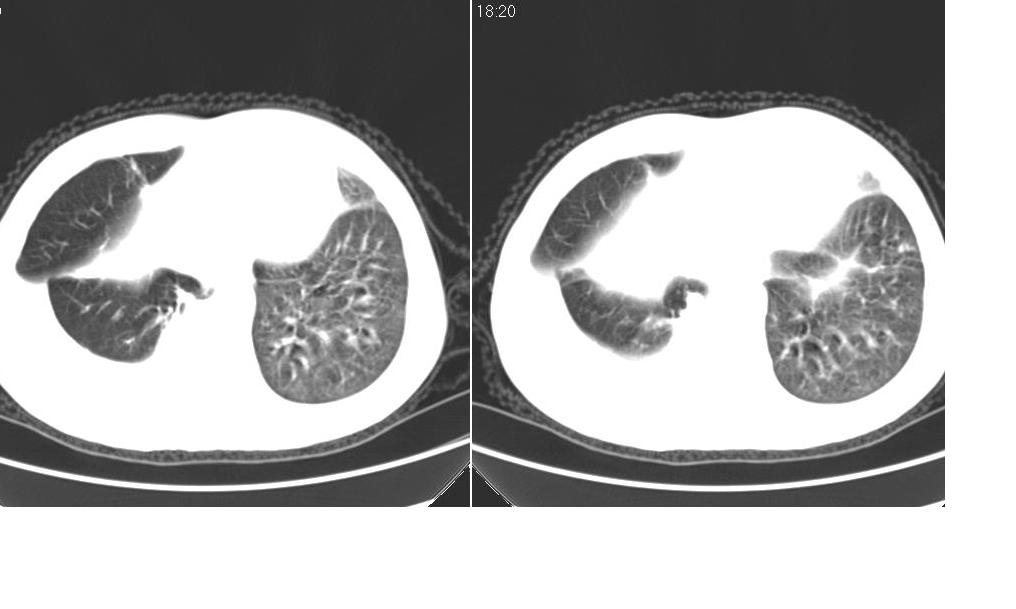

标题: CT10843:男 61岁,胸部CT平扫 [打印本页]

标题: CT10843:男 61岁,胸部CT平扫

男 61岁,已确诊肺癌半年余.

右肺小细胞肺癌并纵隔淋巴结转移。胸腔积液,心包少量积液。左肺改变不除外癌性淋巴管炎

考虑:1、右肺下叶中心型肺癌并纵隔淋巴结转移。胸腔积液。

2、心包少量积液。

3、左肺改变不除外癌性淋巴管炎或化疗后肺间质纤维化。

纵隔及右肺门淋巴结肿转移,右肺改变是否为阻塞性肺气肿改变?左肺改变支持淋巴管炎的诊断;化疗后肺改变应该双肺都有改变。

支持!另:右肺癌性淋巴管炎!